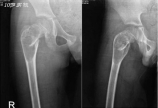

【小儿骨科】“问倒老师系列”之六:儿童股骨近端骨囊肿伴病理骨折

病情概述: 一例儿童股骨近端骨囊肿伴病理骨折的处理策略(EBM分级:专家意见)Seniordoctor:ManuelCassianoNevesMD,MSc(EFORTPresident2013-2014)EFORT:EuropeanFederationofNationalAssociationsofOrthopaedicsandTraumatology………… [详情]